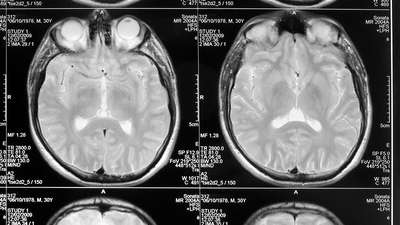

Sekiz yaşındaki kız çocuğunun sürekli geçirdiği epilepsi nöbetinin arkasından öyle bir şey çıktı ki... İsmi açıklanmayan çocuğun beyninde 100 tane tenya yumurtası tespit edildi.

İngiliz gazete Daily Mail'de yer alan habere göre; sürekli epilepsi nöbetleri geçiren ve baş ağrısı çeken sekiz yaşındaki kız çocuğuna, beyninde kist olabileceği düşünülerek, steroid tedavisi verildi. Altı aydan sonra küçük kızın nefesi kesilmeye ve yürüyememeye başladı. Yapılan taramaların ardından minik kızın beyninde 100 tane tenya yumurtası olduğunu tespit ettiler. Beynindeki kurtçuklar çıkarıldıktan sonra küçük kız iyileşti ve yürümeye başladı.

Doktorlar, talihsiz çocuğun beynindeki bu kurtçukların yıkanmamış meyveden ya da pişmemiş domuz etinden kaynaklandığını düşünüyor.